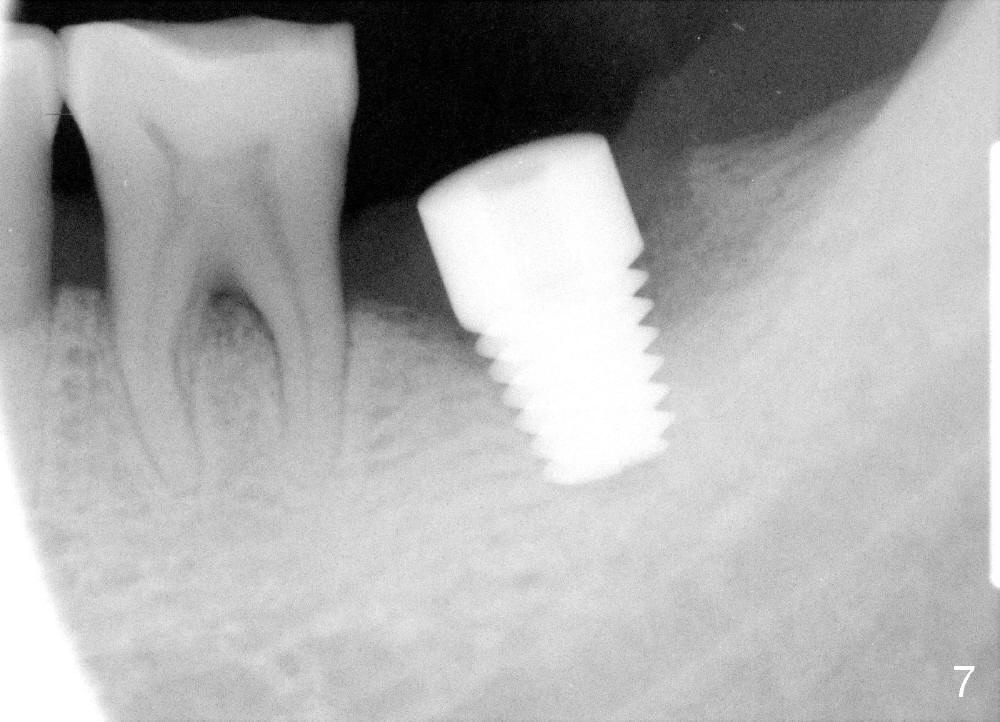

How about flatten the septum (Fig.4 white lines; from inset A (post extraction) to B)? When the septum is level with the mesial and distal sockets, a drill easily penetrates the middle of the socket (Fig.3 inset C). With strict control of depth, the osteotomy increases until a 6x14 mm tap gets initial binding to the socket (Fig.5: depth 11 mm). After increase in the depth by 1-2 mm, PA is taken with a 7x14 mm tap (Fig.6). There is a gap that the tap or the corresponding implant can engage further (between arrowheads). After increase in the diameter in the bottom of the osteotomy, a 7x11 mm implant is placed with insertion torque between 45 and 50 Ncm; the threads of the implant have tight contact with the bone (Fig.7). With the large diameter implant, the socket opening is closed without too much tension (Fig.8). The wound is protected with perio dressing. Postop there is no paresthesia. Pain is controlled by Hydrocodon/Acetaminophen. A long acting local anesthetic (Marcaine) should have been used immediately postop. Next morning, the patient is pain free. A short implant should be used in a critical area such as the lower 2nd molar where the inferior alveolar nerve is nearby. However, the implant is found unstable 1 month postop.